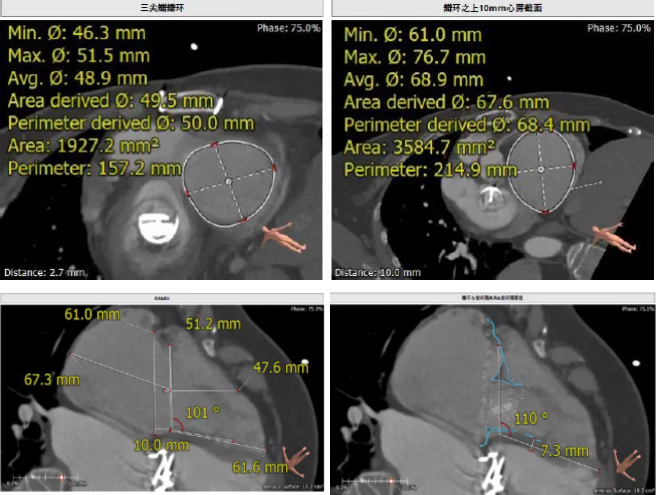

患者64歲女性,18年前接受了“正中開(kāi)胸二尖瓣機(jī)械瓣置換術(shù)”,2年前超聲檢查發(fā)現(xiàn)“三尖瓣重度返流”。輾轉(zhuǎn)多地,嘗試各種治療方式,均無(wú)明顯改善。由于存在相關(guān)合并癥,傳統(tǒng)外科手術(shù)風(fēng)險(xiǎn)大,郭惠明教授團(tuán)隊(duì)結(jié)合該患者CT、超聲檢查結(jié)果,對(duì)該患者的情況進(jìn)行了充分的評(píng)估和討論,決定采用LuX-Valve人工三尖瓣介入瓣膜置換系統(tǒng)對(duì)患者進(jìn)行微創(chuàng)介入治療,以最小的創(chuàng)傷解決患者的病痛。

術(shù)前CT評(píng)估